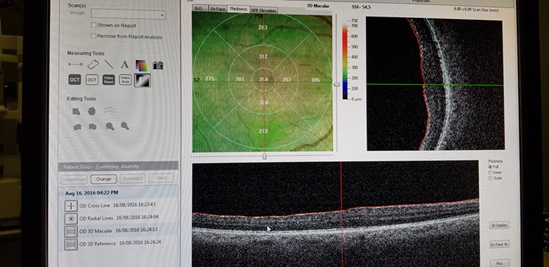

Пациент увидел шесть строчек. Но появились жалобы на искажение. Причиной этого стала сформированная эпиретинальная мембрана (похожа на целлофановую пленку, покрывающую сетчатку) в центре. При этом новый хрусталик стоял отлично, а роговица сохраняла стабильность.

На компьютерной томограмме видно правильное положение новой линзы под радужкой

Девятнадцатая операция – удаление эпиретинальной и внутренней пограничной мембран – выглядит так: витрэктомия + работа в полости стекловидного тела специальными пинцетами для удаления вручную «целлофана». Опять же когда видно плохо. Но все удалось – результат 80% зрения, а коррекцией все 90-100% (мешает все-таки роговичный астигматизм).

Давление хорошее, без капель. Положение хрусталика нормальное. Роговица — по-прежнему иррегулярная, плотность и качество эндотелия не очень высокие. Но прозрачность хорошая и позволяет видеть 100%.

Это томограмма мембраны, вызывающее искажение рельефа сетчатки

Томограмма сетчатки после 19-й операции